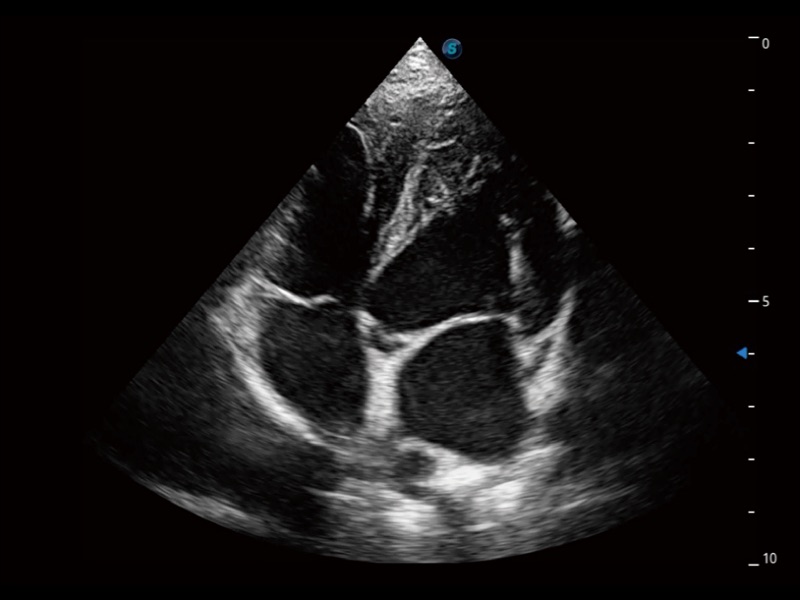

优异的基础图像

ProPet 70 全新的动物超声智能软件和丰富的探头群,为动物医生提供了高清晰度和精细分辨率的图像,无论在宠物、马科、畜牧还是实验室动物等应用中都可以轻松应对,为您的日常工作带来满意的体验。

(犬)四腔心

(犬)四腔心MQA